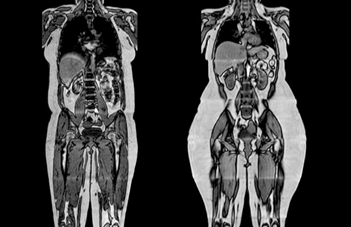

而海豚看人類(lèi)還有第二個(gè)維度,大概就是這樣的。。。

給你了一個(gè)做實(shí)時(shí)B超

海豚的聲納能夠穿透人體,而同為哺乳動(dòng)物在身體結(jié)構(gòu)上也很相似,這也使得海豚在嗅覺(jué)之外分辨人類(lèi)性別輕而易舉。

海豚發(fā)出的超聲波聲強(qiáng)最大能達(dá)到8W每平方厘米,可以穿適幾十厘米的沙土發(fā)現(xiàn)藏在下面的魚(yú),而我們用B超檢查身體時(shí)的聲強(qiáng)不超過(guò)80mW,作為治療用途時(shí)一般也不會(huì)超過(guò)2W。所以對(duì)于海豚來(lái)說(shuō),人類(lèi)的皮膚、肌肉和脂肪等幾乎是適明的.